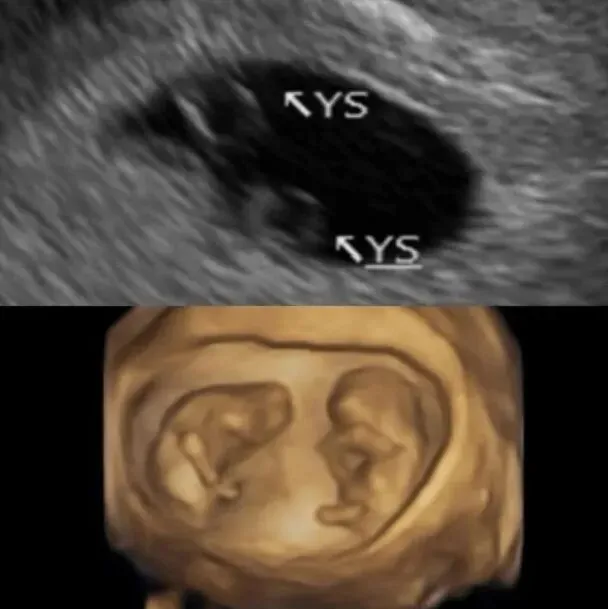

台湾女星郑家纯(鸡排妹)近日于社文网大晒超音波照片,宣布已怀孕12周的好消息。

没料到于农历年除夕那天,验孕棒出现淡淡的第两条线,经过日本、台湾双重产检,确定成功怀上双胞胎。

不过她只有惊喜了一下子:「因为同卵双胞胎比异卵的风险高,还有分单羊膜还是双羊膜。宝宝们很贴心,让我在6周就听到心跳,听到的瞬间眼泪就掉下来,因为上次没有听到。产检后有勇气再度开始写怀孕日记。」